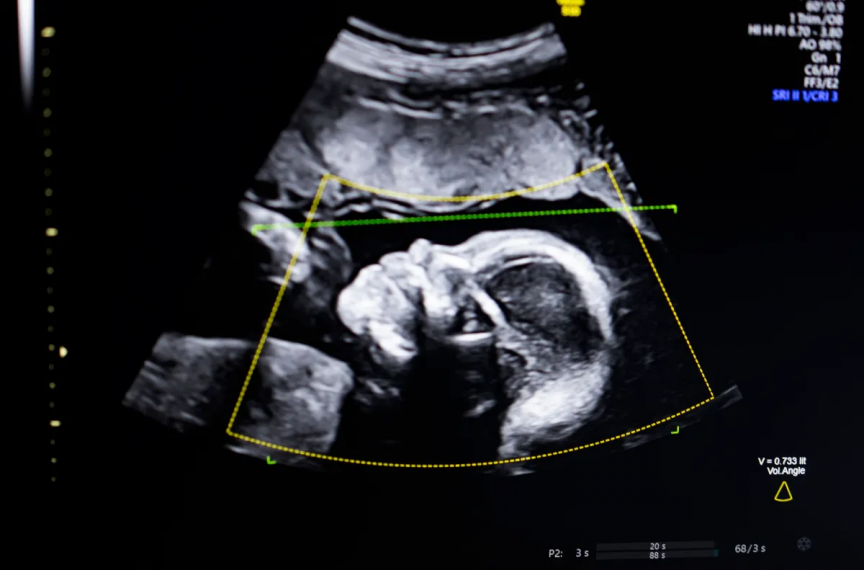

އަލްޓްރާސައުންޑުން ކުއްޖާގެ އައިބުތައް ދެނެގަންނަން ދުނިޔޭގައި ފުރަތަމަ އުފެއްދި އޭއައި ސޮފްޓްވެއާއަށް އެމެރިކާގެ ފުޑް އެންޑް ޑްރަގް އެޑްމިނިސްޓްރޭޝަން (އެފްޑީއޭ)ގެ ހުއްދަ ލިބިއްޖެއެވެ.

ބުސްތާމީ ވިދާޅުވި ގޮތުގައި މި ޓެކްނޮލޮޖީ ބޭނުންކުރަނީ "ކޮމްޕިއުޓަރު ވިޜަން އޭއައި" އެވެ. މީގެ އެހީގައި އަލްޓްރާސައުންޑްގެ ފެންވަރު ބެލުމާއި، ކުއްޖާގެ ގުނަވަންތައް ފުރިހަމައަށް ހުރިތޯ ބެލުމުގެ އިތުރުން، އޮޓޮމެޓިކުން ރިޕޯޓްތައް ތައްޔާރުކޮށްދީ ކްލިނިކަލް މަސައްކަތްތައް ފަސޭހަކޮށްދެއެވެ.

މި ޓެކްނޮލޮޖީ އުފެއްދުމުގެ މައިގަނޑު މަގުސަދަކީ އެމެރިކާގައި މާބަނޑު ދުވަސްވަރު ދިމާވާ ސިއްހީ މައްސަލަތަކާއި، މަރުވާ މީހުންގެ އަދަދު މަދުކުރުމެވެ. ޚާއްޞަކޮށް ކަޅު ނަސްލުގެ އަންހެނުންގެ މަރުގެ ރޭޓް މަތިވުމާއި، އަލްޓްރާސައުންޑް ތަސްވީރުތަކުގެ ފެންވަރު ދަށްވުމުގެ ސަބަބުން ދިމާވާ ނުބައި ޑައިގްނޯސިސްތަކަށް މީގެ ސަބަބުން ހައްލެއް ލިބޭނެ ކަމަށް އޭނާ އުންމީދު ކުރައްވައެވެ.

މި ސޮފްޓްވެއާ ތަމުރީނުކުރުމަށް އެތައް ލައްކަ އަލްޓްރާސައުންޑް ތަސްވީރުތަކެއް ބޭނުންކޮށްފައިވެއެވެ. ބުސްތާމީ ވިދާޅުވީ، އެންމެ އުނދަގޫވި ކަމަކީ ހަމައެކަނި އޭއައި މޮޑެލް ބިނާކުރުން ނޫން ކަމަށާއި ނަމަވެސް ތަފާތު އެކި ނަސްލުތަކުގެ މީހުންނަށް މި ޓެކްނޮލޮޖީ އެއްވަރަކަށް މަސައްކަތްކުރާކަން ކަށަވަރުކުރުން ކަމަށެވެ.